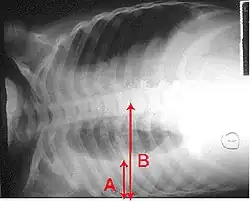

Op een longfoto is pleuravocht zichtbaar als een wit gedeelte op de longfoto.[4] Op een normale thorax foto is de ruimte tussen de viscerale pleura en de pariëtale pleura niet zichtbaar. Wanneer er pleuravocht aanwezig is, is deze ruimte wel zichtbaar. De densiteit van pleuravocht is ongeveer gelijk aan die van water, hierdoor is dit witter op een longfoto in vergelijking met de rest van de long (die meer de densiteit van lucht heeft). Door de hogere densiteit zal pleuravocht zich altijd bevinden op het laagste punt van de thoraxholte en is er een bij horizontale vloeistofspiegel (meniscus).[5] Een longfoto in zijligging (op de zijde waar het pleuravocht zich bevindt) is sensitiever voor pleuravocht. Dit wordt een "decubitus opname" genoemd, bij deze opname wordt een hoeveelheid van 50 ml of meer pleuravocht zichtbaar. Een CT-scan van de borstkas is het meest nauwkeurig voor het bepalen van de aanwezigheid van pleuravocht, maar ook de hoeveelheid en kenmerken van het pleuravocht. Ook echografie kan gebruikt worden om pleuravocht aan te tonen.[6]

Pleuravocht te zien op een laterale longfoto (een longfoto vanaf de zijkant).